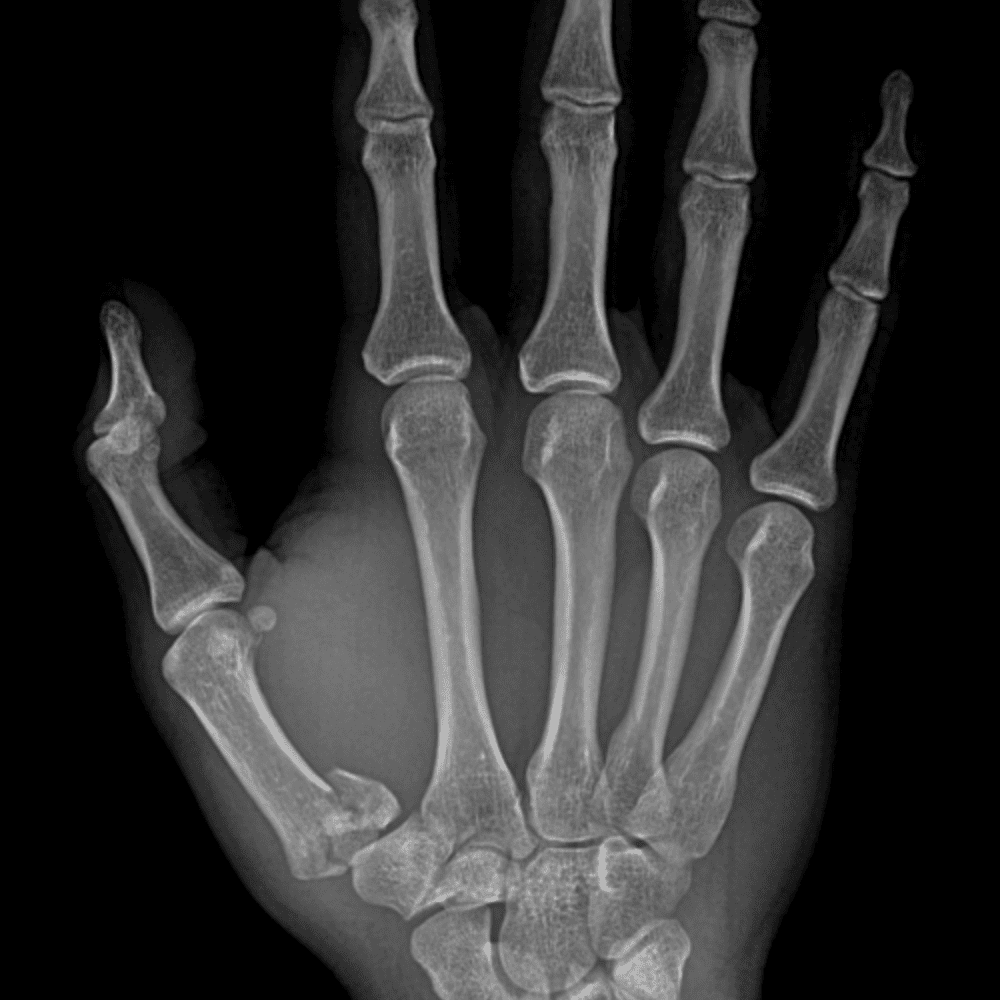

Simuliert den Dienst durch subtile oder schwierige Fälle und einige Normalbefunde.

30 Fälle